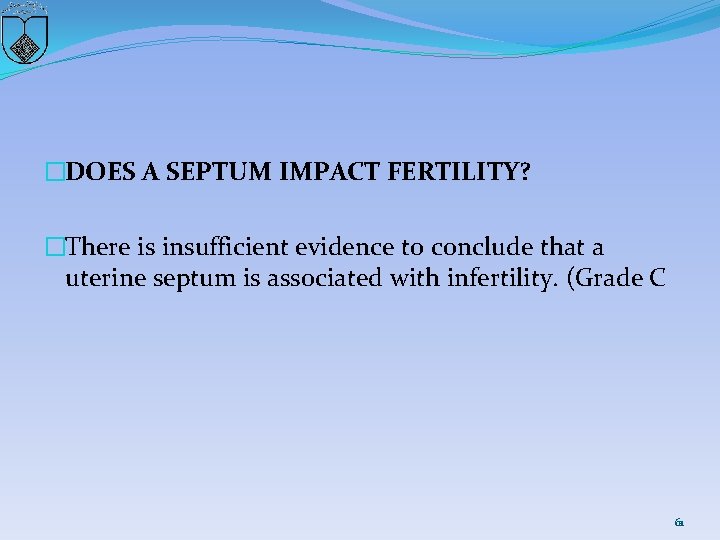

�DOES A SEPTUM IMPACT FERTILITY? �There is insufficient evidence to conclude that a uterine septum is associated with infertility. (Grade C 61